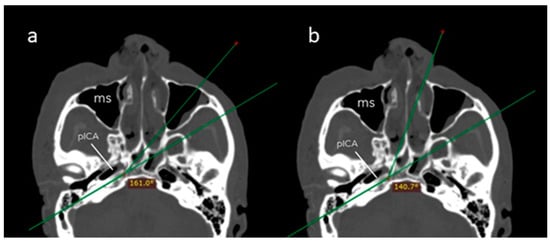

2.3. Quantitative Analysis and Surgical Operability

3.1. Anthropometric Measurements and Surgical Operability

| Angle of attack (°) | 161.1 (8.6) | 140.6 (5.7) | 0.001 |

| Surgical field depth (mm) | 74.3 (4.0) | 88.0 (5.8) | 0.001 |

| Petrous drilling depth (mm) | 17.2 (4.0) | 11.0 (3.3) | 0.008 |